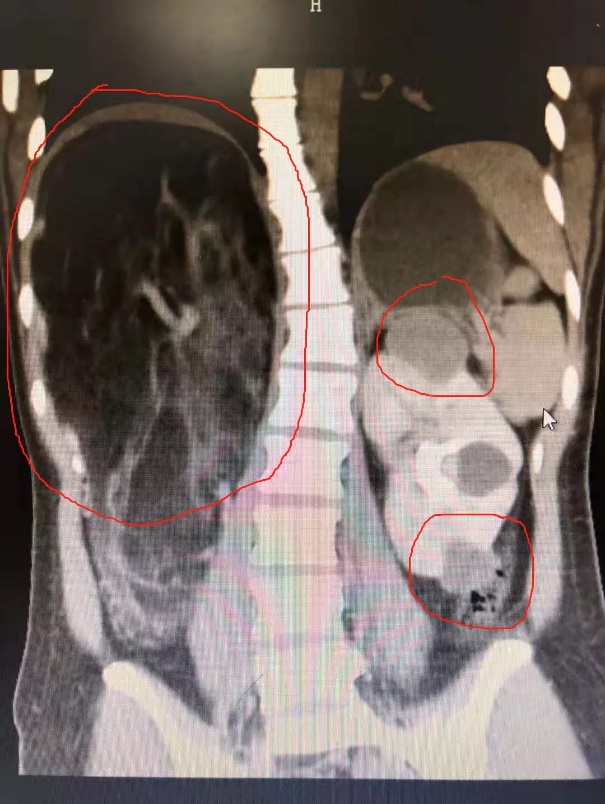

胸片显示脊柱侧弯、红圈内容为双肾肿瘤

广医五院泌尿外科,有一个特殊的年轻病人心心——她,一头乌黑的秀发,却独在额头有一撮花白。年仅20岁,身材高挑、爱笑,正是爱美的花样年华,却已被确诊有癫痫、脊柱侧弯左肾多发肿瘤、右肾巨大肿瘤,上顶肝脏、后压腰椎。

术中发现,右肾肿物直经接近30公分,与肝脏、脾脏和肠道等体内重要器官紧贴着,经过医生的共同努力,终于切除了双侧肾脏肿物,右肾取出肿物重达4.6斤,约相当于20倍正常肾脏重量!在这样的手术难度下,泌尿外科团队成功为心心保留双侧肾脏!